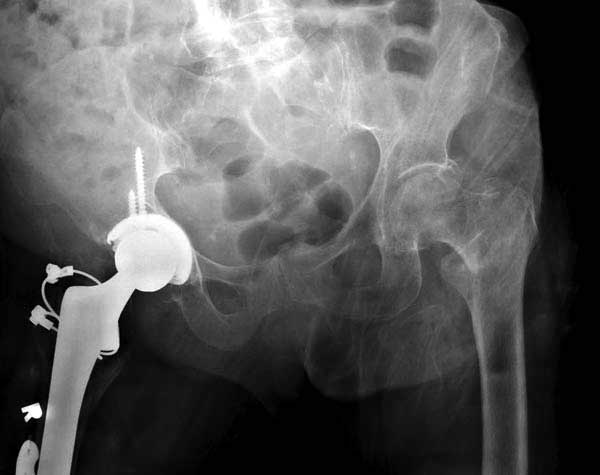

Третья операция-продолжения усилии "синьорами пэрами" по разрушению нормальной анатомии. Крест на головку! По видимому возраст позволяет биполярную конструкции, и при дефекте  calcar пошли на обычный цементный. Ягодичные мышцы потеряли связь с вертелом, т.е. отсутствует верхний удержатель, и результат “a Big Screw Up!” Снимки вызывают головокружение!

Если хирурги не устали от своих “творчеств”, тогда можно ре-оперировать с calcar replacement stem, и собрать остаток ягодичных мышц. Глубина и отстутствие артроза позволяет применить любой, биполярный или тотальный, хотя принять решение можно после ревизии ацетабулума.